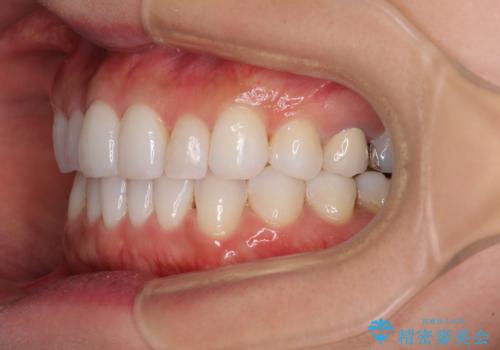

軽度の叢生をインビザライン・ライトで解消

- 前歯が気になるとのことで来院された患者様です。

歯列不正は軽微であったため、インビザライン・ライトにより、費用を抑えて矯正治療を行うこととしました。

短期間で気になる前歯の歯列を改善することができました。